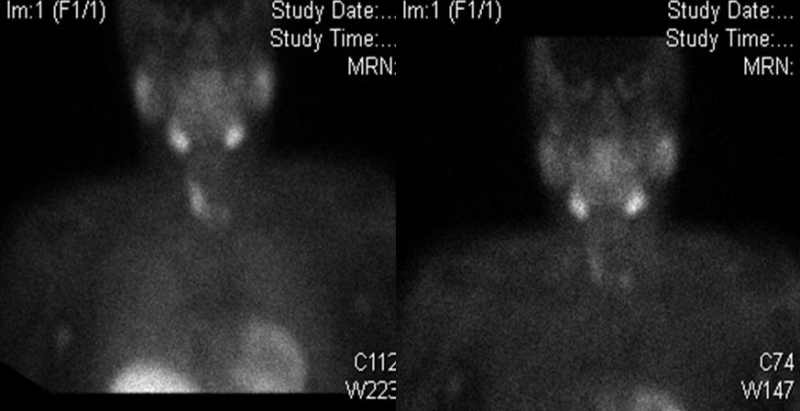

Las proyecciones de cabeza, cuello y tórax se realizaron a los 10 minutos y 2 horas después de la administración de 795 MBq de 99mTc-MIBI. La etapa inicial mostró captación del trazador limitada al lóbulo tiroideo derecho, el istmo y una región correspondiente al lecho tiroideo inferior izquierdo. En la fase tardía, se observó captación focal persistente en la región inferior del lecho tiroideo izquierdo (fig. 1).